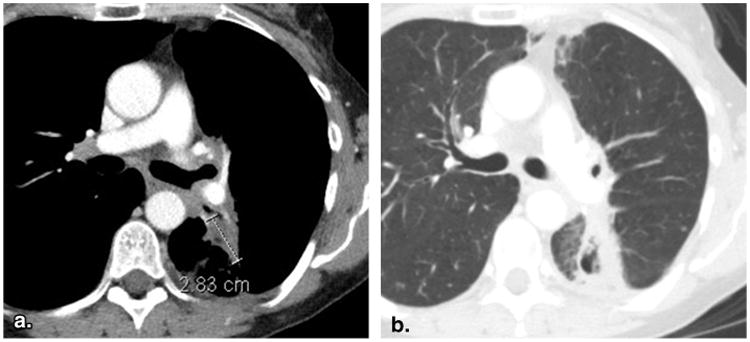

Figure 2.

Inappropriate selection of a target lesion from within a radiation field (53-year-old female with non-small cell lung cancer). Baseline contrast-enhanced computed tomography of the chest viewed at soft tissue window settings (a) reveals a lesion in the left lung that was designated as a target lesion. However, the same slice viewed at lung window settings (b) demonstrates surrounding linear parenchymal fibrosis characteristic of previous radiation. The previous radiation would disqualify this lesion as a target lesion, unless unequivocal progression after radiation had been previously demonstrated.